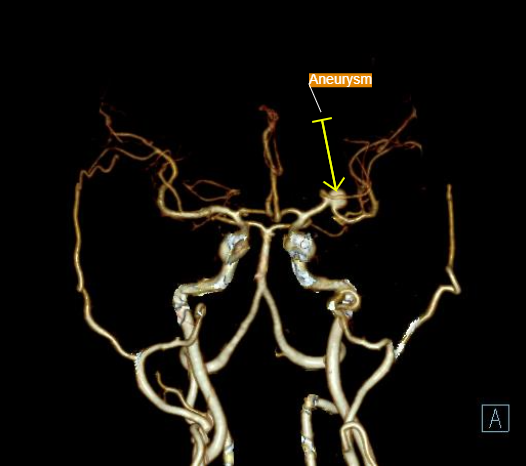

3D VRT Image anterior view Aneurysm of opercular segment of left middle cerebral artery.

• Aneurysmal dilatation ( 7.10mm in diameter) is seen in opercular segment of left middle cerebral artery.